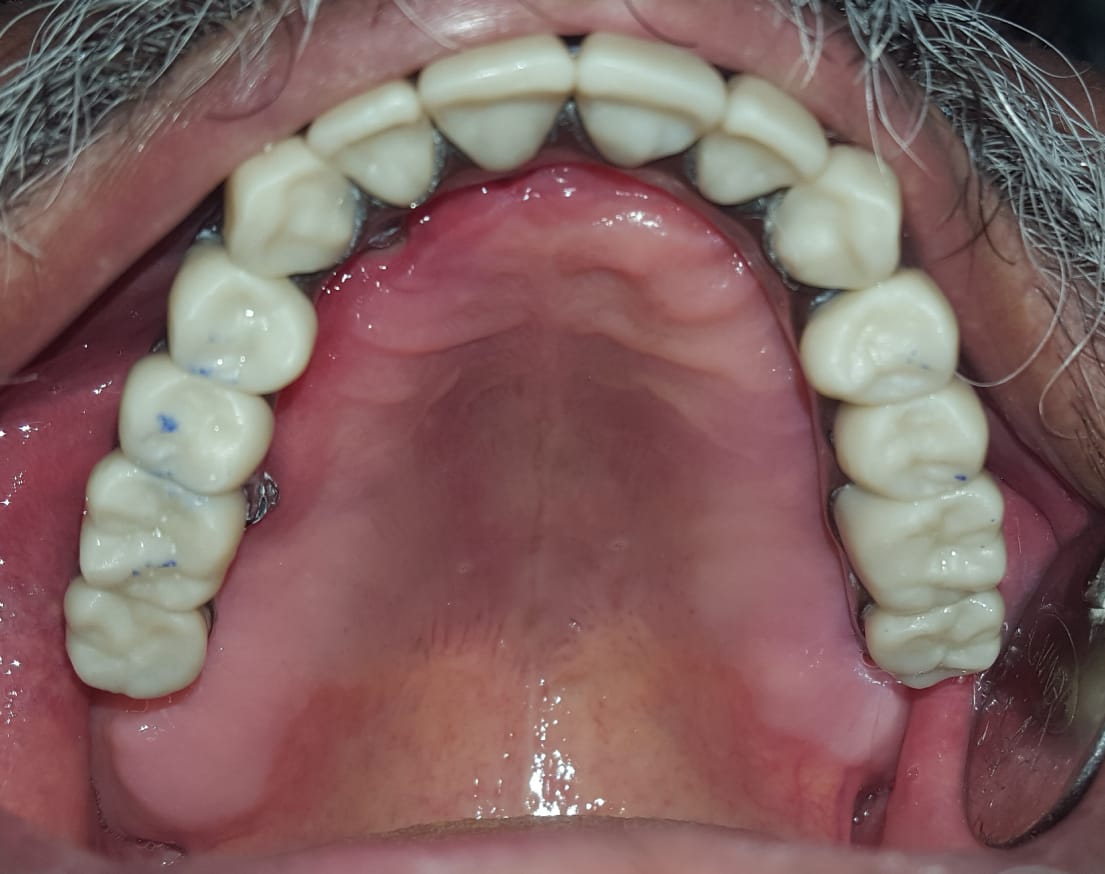

Full Mouth Implants with all Ceramic Crowns

Mr. Ramnani (Florida, USA)